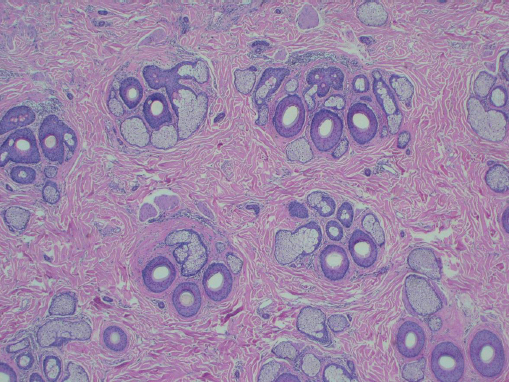

Hair follicles of the scalp naturally exist as follicular units ( Fig. 28.2 ). The follicular unit consists of one to four terminal hairs with or without several vellus hairs, a sebaceous gland and duct, arrector pili muscle, and a common vascular and neural plexus. The entire unit is surrounded by a connective tissue sheath. Using microscopy, the structure of the follicular unit and the surrounding area of non–hairbearing skin is visible ( Fig. 28.3 ).